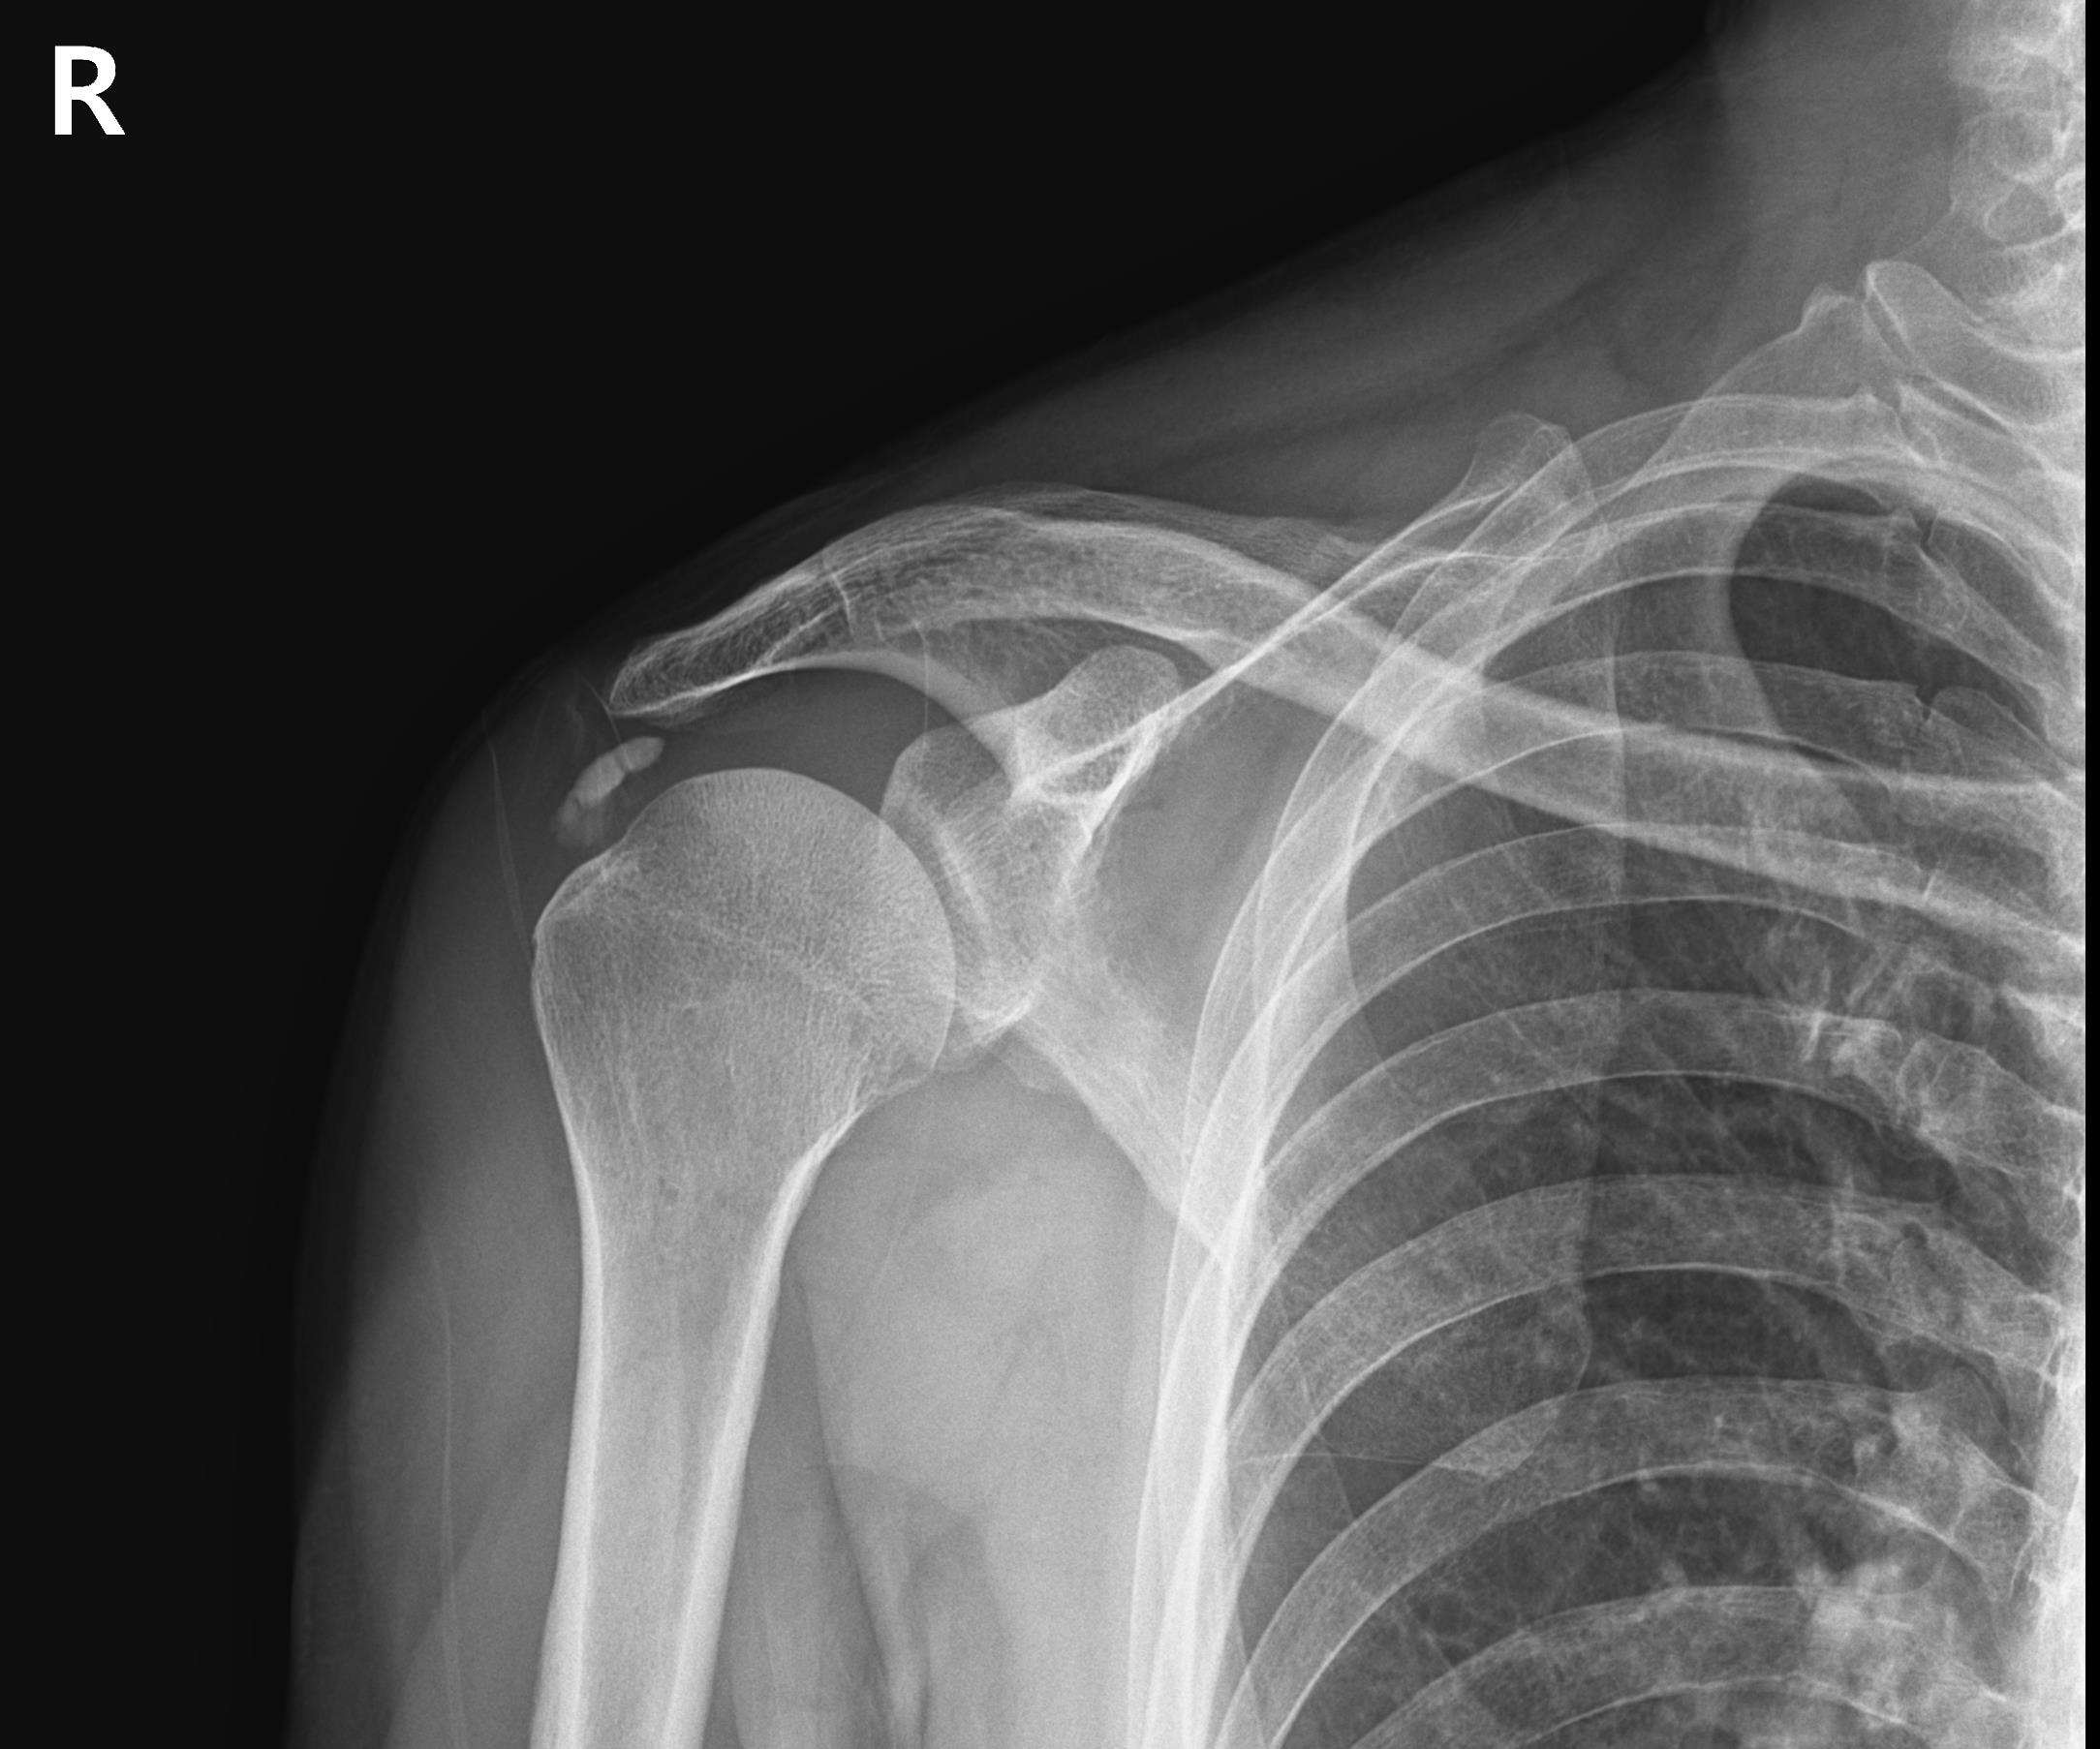

X-ray와 MRI, 초음파 검사를 시행했습니다.

진단 결과:

- ✓석회성건염: 극상건에 약 1.4cm 석회 (휴지기)

- ✓회전근개 관절면측 부분파열: 약 40%

두 가지 문제가 동시에 있었습니다.